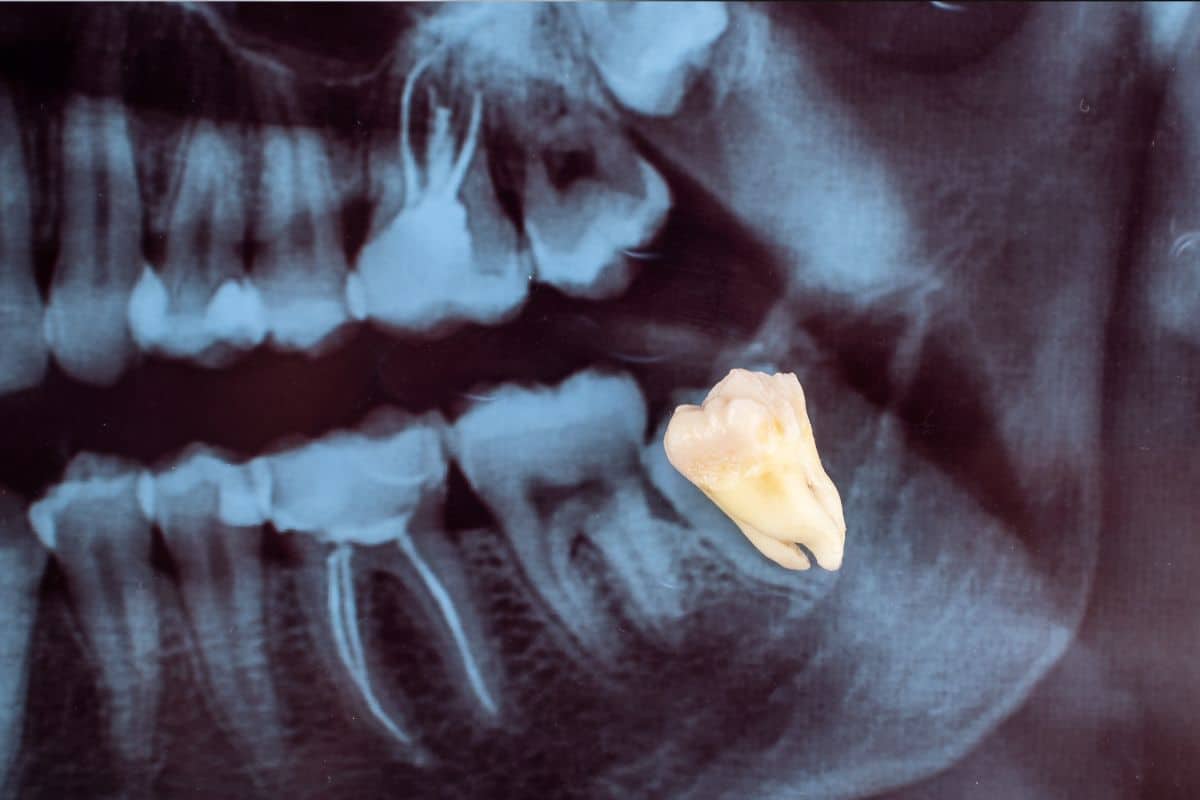

When you visit your Henderson dentist for an emergency consultation, they will conduct a thorough examination of your mouth. This may include X-rays to determine the position and condition of your wisdom teeth.

The extraction process varies depending on whether your wisdom teeth are fully erupted or impacted. For fully erupted teeth, a simple extraction is performed. If the teeth are impacted, a surgical extraction may be necessary. This involves making an incision in the gum to access the tooth and remove it.